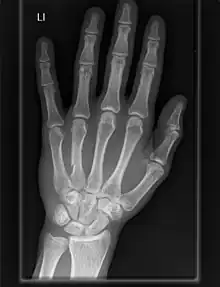

Articulación carpometacarpiana

Las articulaciones carpometacarpianas (CMC) son cinco articulaciones de la muñeca que articulan la fila distal de los huesos del carpo y las bases proximales de los cinco huesos metacarpianos.

Dedos

- El segundo metacarpiano se articula principalmente con el trapezoide y secundariamente con el trapecio y el capitado.

- El tercer metacarpiano se articula principalmente con el capitado,

- El cuarto metacarpiano se articula con el capitado y el hueso ganchoso.

- El quinto metacarpiano se articula con el hueso ganchoso.[7]